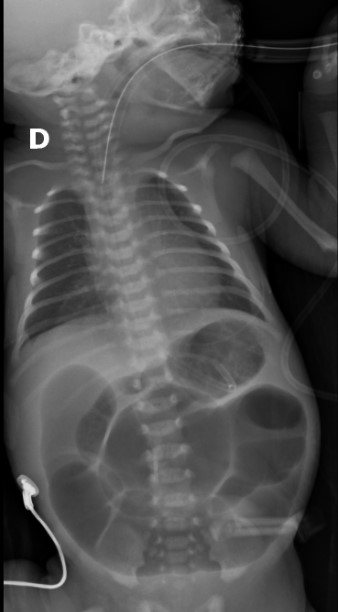

Se presenta el caso de una paciente de 23 años de edad, secundigesta, sin antecedentes personales ni familiares de relevancia. La paciente adjunta el estudio de screening de aneuploidías de la semana 11-14, que arroja bajo riesgo. Las imágenes 1 y 2 describen los hallazgos identificados durante la evaluación de la anatomía fetal en la semana 12. Las imágenes 3, 4 y 5 corresponden a los controles ecográficos posteriores, del segundo y tercer trimestre. La imagen 6 muestra al recién nacido. Seleccione la opción correcta: A. Corresponde a una hernia umbilical fisiológica con resolución más tardía. B. Corresponde a una gastrosquisis con cierre espontáneo intraútero. C. Corresponde a un onfalocele con ruptura del mismo. D. El defecto de pared cerró espontáneamente mejorando el pronóstico y riesgo de complicaciones gastrointestinales. Figura 1: se visualiza corte axial del abdomen fetal, a nivel de la inserción del cordón umbilical, con Doppler color en semana 12. Figura 2: se observa corte axial, a nivel de la inserción del cordón umbilical en la pared abdominal anterior, en semana 12. Figura 3: corte sagital a nivel de la inserción del cordón en la pared abdominal anterior, con Doppler color, en semana 20. Figura 4: corte axial del abdomen fetal, en semana 32, donde se identifica dilatación de las asas intestinales. Figura 5: corte axial del abdomen fetal, en semana 32, donde se identifica dilatación de las asas intestinales, con la utilización del Doppler color. Figura 6: se observa al recién nacido.

A partir de ese momento se realizó un seguimiento ecográfico exhaustivo, evidenciándose una dilatación progresiva del intestino intra-abdominal, entre 10.5 mm en semana 25 (Figura 4) a 26.5 mm en semana 34, siempre con aparente indemnidad de la pared abdominal (Figura 5). La progresión biométrica fue acorde a la edad gestacional, con Doppler fetoplacentario y valoraciones de líquido amniótico normales. En el último control ecográfico de la semana 34, el equipo de obstetricia, en conjunto con neonatología, deciden la finalización del embarazo por cesárea abdominal. El recién nacido fue de sexo masculino, con un peso de 2760 gs, adecuado para la edad gestacional, Apgar 6/8, y al examen físico presentó indemnidad de la pared abdominal anterior  (Figura 6). Se realiza una ecografía abdominal y radiografía de abdomen, confirmando la dilatación intestinal generalizada (Figura 7).  A las 72 horas de vida, se realiza laparotomía exploradora donde se identifican asas intestinales obstruidas a nivel de íleon y colon derecho por lo que se procede a la resección de las mismas con reconstrucción del tránsito mediante la anastomosis yeyuno colónica término-lateral y yeyunostomía en fosa ilíaca derecha. Actualmente, se encuentra en seguimiento por servicio de cirugía y gastroenterología pediátrica.